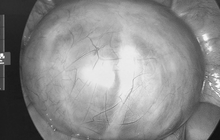

Nếu đột nhiên thấy nhiều đốm đỏ nổi lên trên khuôn mặt nhưng không gây ra cảm giác ngứa ngáy, đi kèm với tình trạng kinh nguyệt không đều, đau bụng dưới thì bạn nên cảnh giác với các bệnh ở tử cung hoặc buồng trứng. Hãy chủ động đi khám ngay để ngăn ngừa sự xâm lấn của nguy cơ mắc bệnh ung thư cổ tử cung.